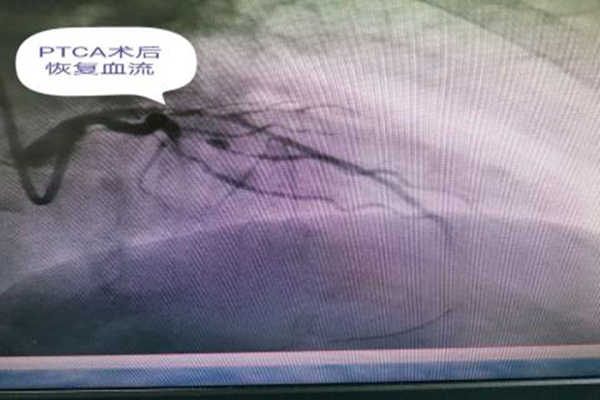

67歲的景大爺晚餐飽食后,突然感到持續(xù)胸痛、胸悶隨后出現(xiàn)全身大汗伴乏力,當(dāng)時(shí)家人都不在家,老人聯(lián)系家屬后,家屬及時(shí)撥打我院急救電話(huà),急救醫(yī)生到達(dá)后做心電圖檢查示急性廣泛前壁ST段抬高型心肌梗死。我院120醫(yī)生把患者的心電圖發(fā)入16醫(yī)院胸痛中心群內(nèi),一邊緊急救治一邊快速、明確地向景大爺家屬告知手術(shù)必要性及手術(shù)的高風(fēng)險(xiǎn)性,并迅速開(kāi)通胸痛中心綠色通道,通知導(dǎo)管介入手術(shù)室做好術(shù)前準(zhǔn)備。征得家屬的同意后立即將患者送入導(dǎo)管介入手術(shù)室行急診冠脈造影術(shù)。心內(nèi)科郭應(yīng)先主任及許慶華副主任立即冠脈造影示:左前降支近段閉塞,及時(shí)給于PTCA術(shù)治療,術(shù)后恢復(fù)2級(jí)血流,擇期行支架植入治療。心內(nèi)科郭應(yīng)先主任醫(yī)師說(shuō):“患者三支血管,一支完全閉塞,兩支次全閉塞,當(dāng)天我們?yōu)槠浯蛲?/span>罪犯血管——左前降支動(dòng)脈,待患者情況穩(wěn)定后,一周后擇期為其開(kāi)通右冠狀動(dòng)脈和左回旋支動(dòng)脈”。隨后,患者生命體征平穩(wěn),轉(zhuǎn)入了監(jiān)護(hù)病房。

血管閉塞

PTCA術(shù)后恢復(fù)血流